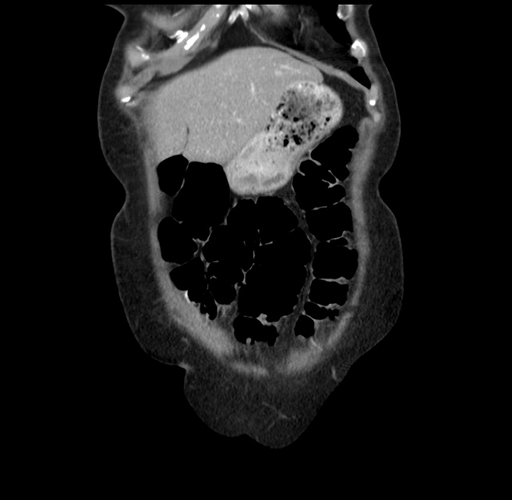

Coronal Venous